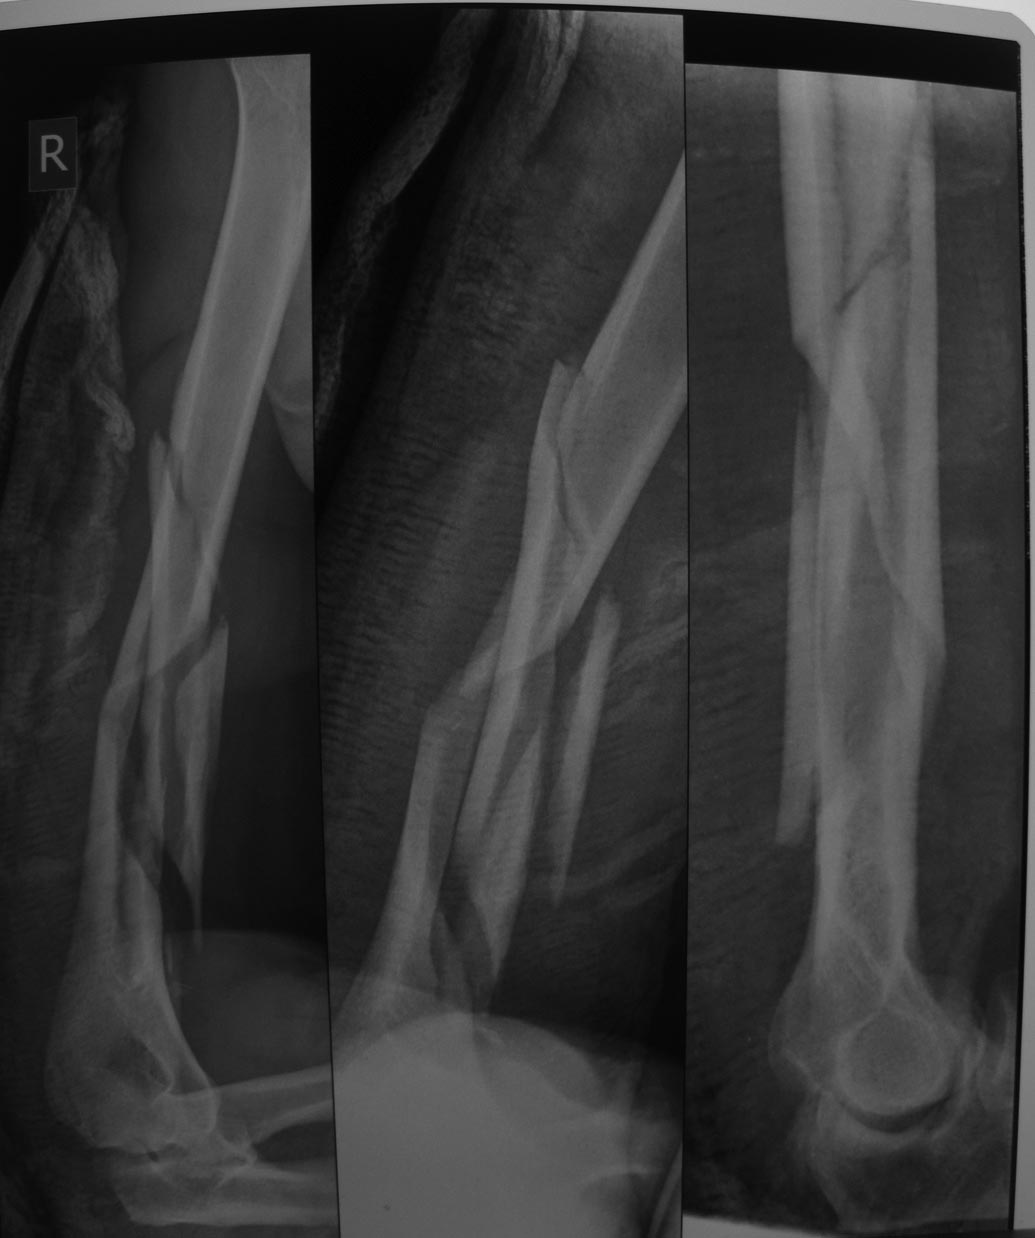

Первичный снимок и контроль(13.03.14) в циркулярной гипсовой повязке

Доброго времени суток! Линия перелома дистально проходит по краю костно-мозгового канала(завтра выложу ещё снимок), поэтому и сомневаюсь в возможности интрамедуллярного остеосинтеза( возможности и определённый опыт есть). Сегодня наложил короткую циркулярную повязку, попытавшись устранить осевые смещения, завтра выложу контрольные рентгенограммы.